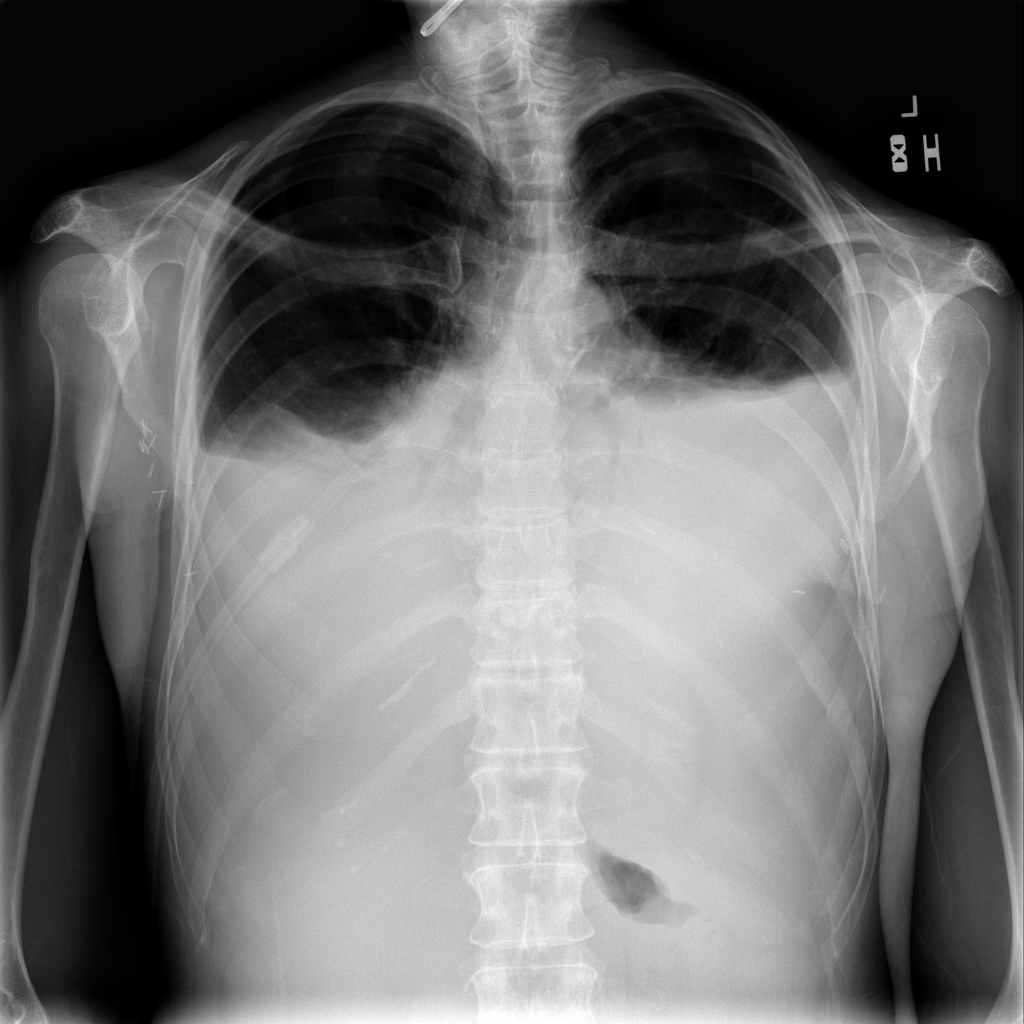

PAT-86C8 · IMG-000Effusion

PAT-86C8 · IMG-000

PA